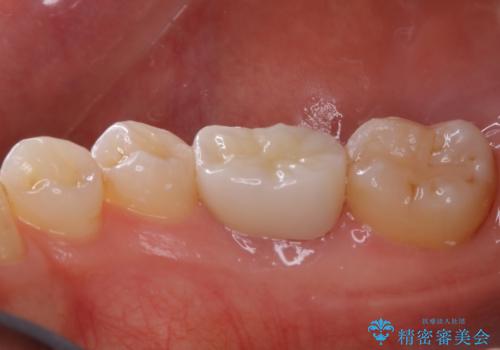

- 歯が欠けてしまったと来院された方です。

メタルインレーが一部欠けており、その下には大きな虫歯ができていました。

再精密根管治療もご提案しましたがご希望されなかったため、今回は土台と被せ物のみ治療介入しました。